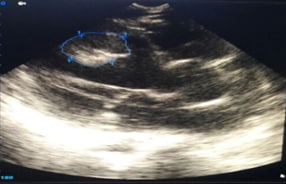

The main task for bed echocardiography in a new coronavirus infection is to assess:

1. global and regional contractile function of the LV and right ventricle (RV) (qualitatively);

2. the size of the heart chambers (dilatation of the chambers);

3. the presence of fluid in the pericardial cavity and in the pleural cavities;

4. presence of mitral regurgitation (qualitatively);

5. the presence of additional formations in the cavities and structure of the heart (blood clots);

6. volemic status (diameter of the inferior vena cava);

7. Ultrasound profile of the lungs .